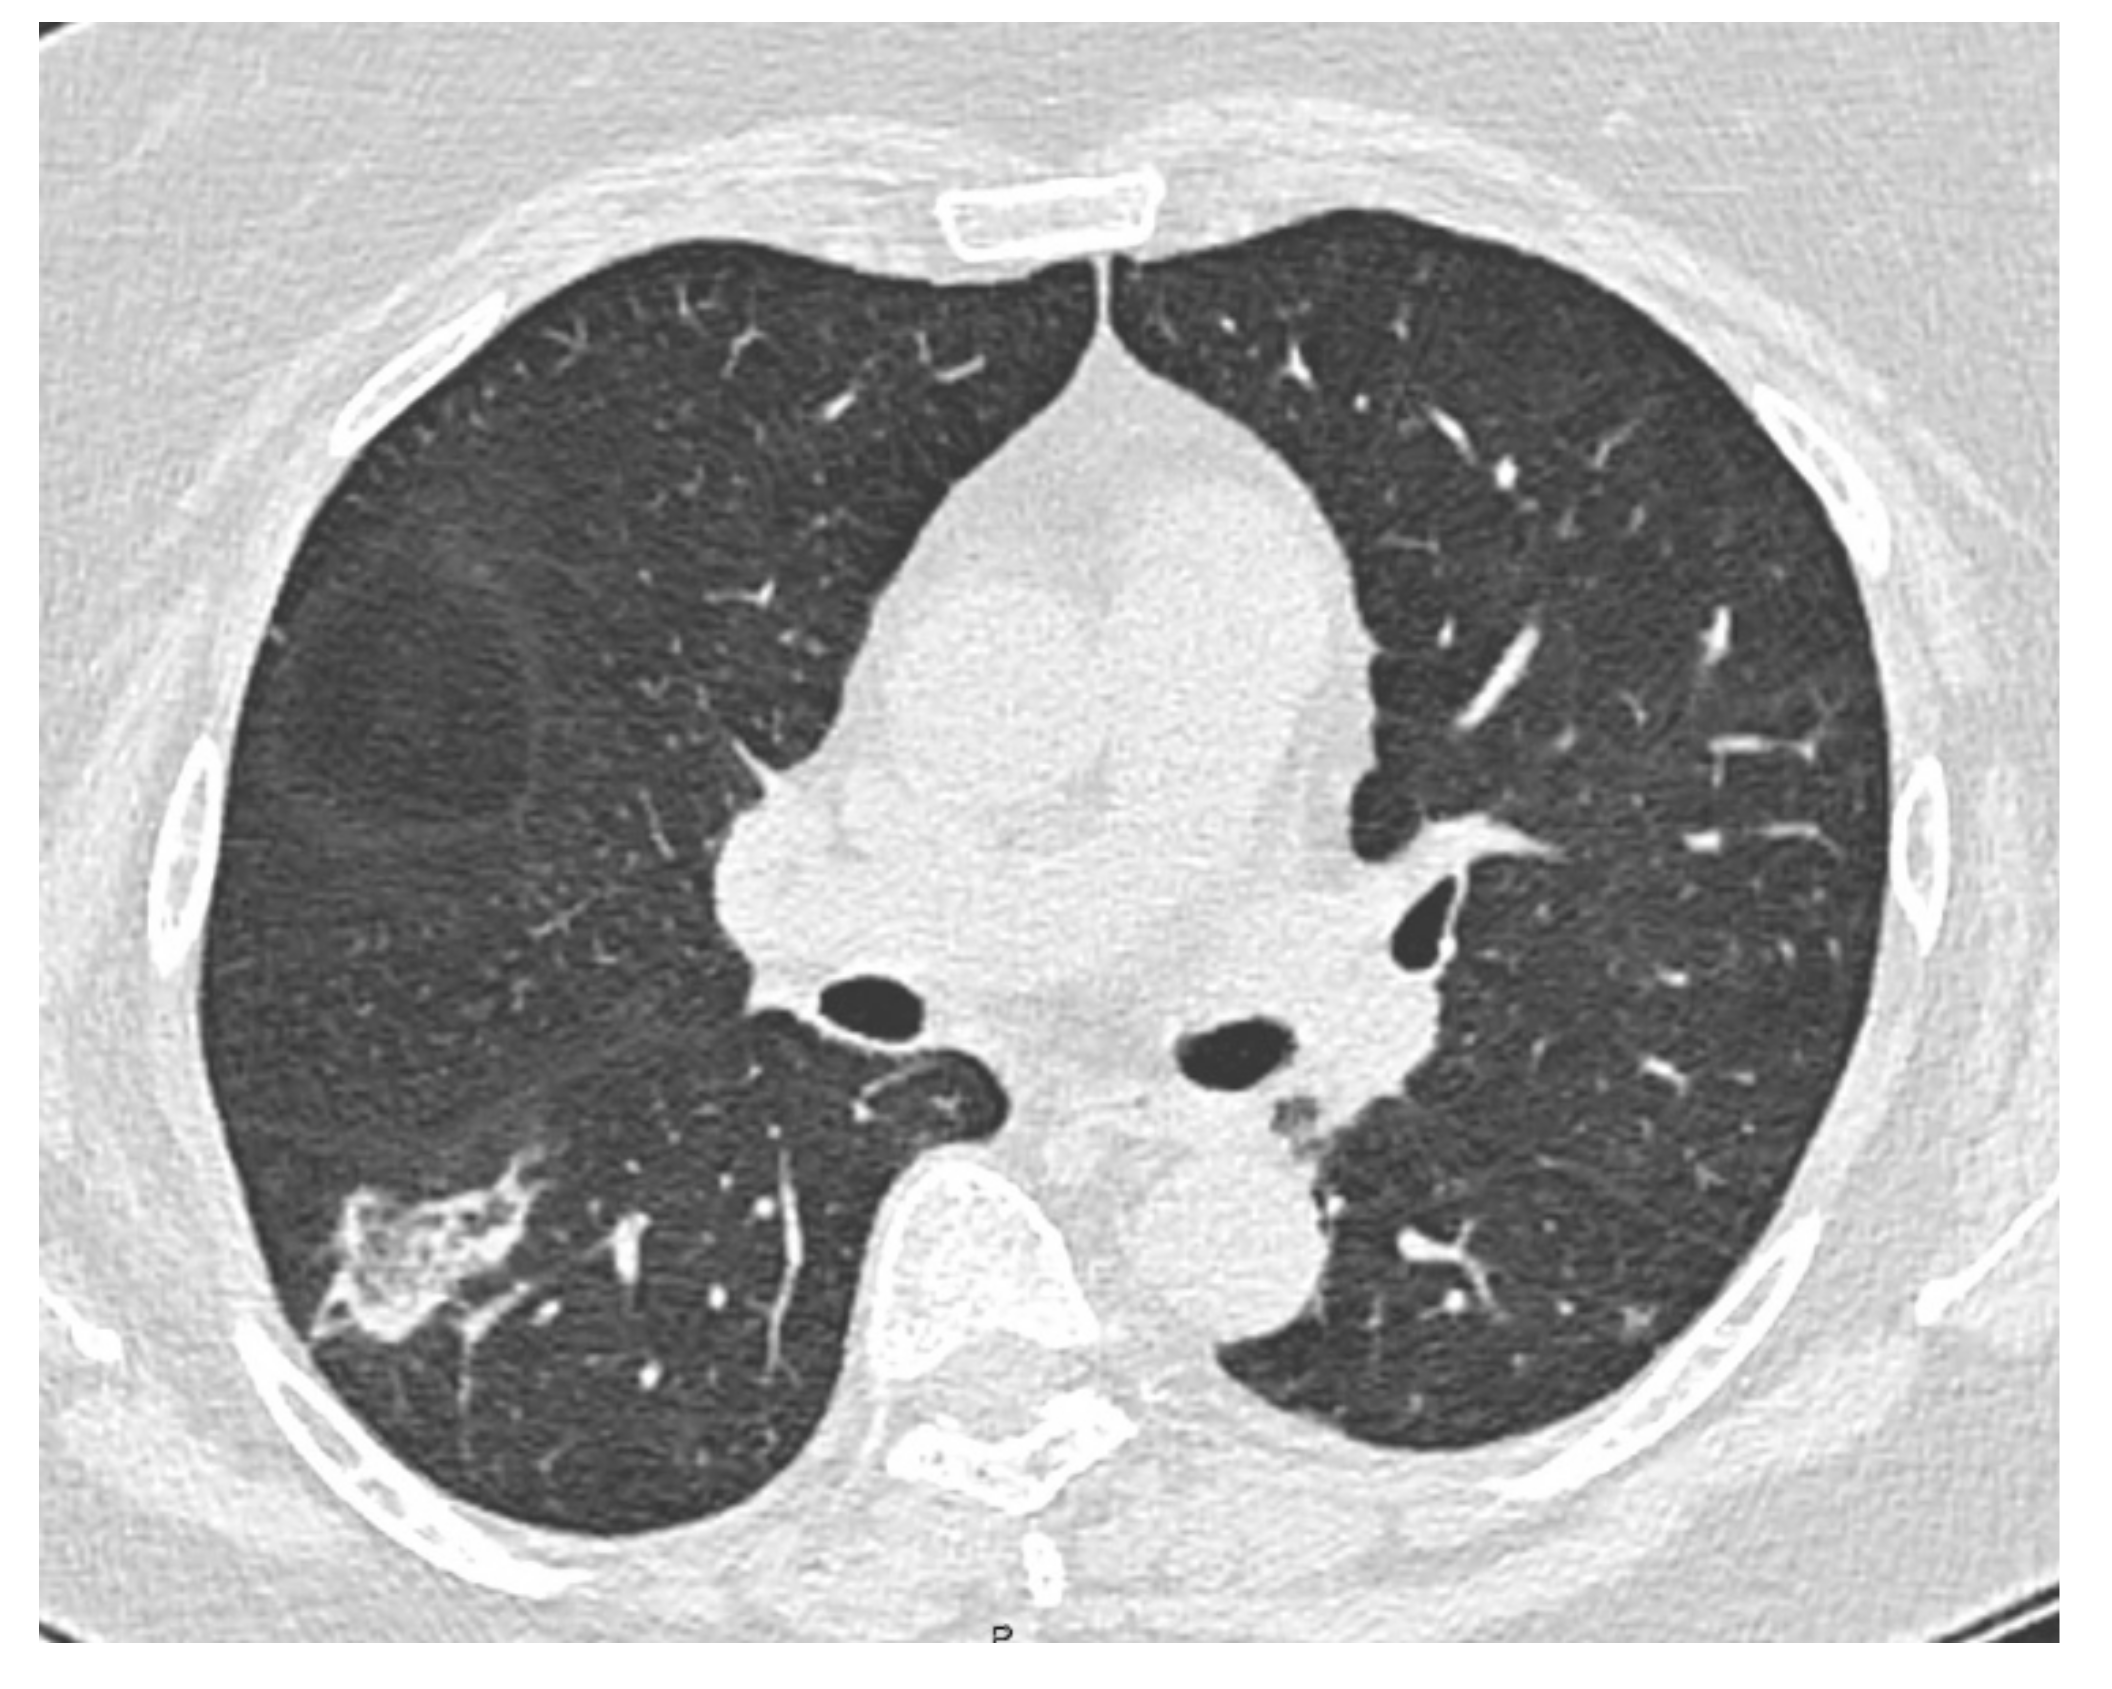

2. Case Presentation